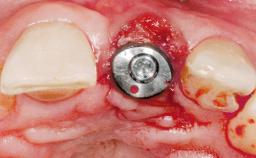

Immediate Flapless Placement of an Implant in a Maxillary Left Central Incisor Site

A 29-year-old female patient presented for treatment to replace the upper left central incisor tooth with an implant- supported restoration. The tooth had been intermittently symptomatic for the previous 12 months. The tooth had originally suffered trauma about 15 years previously. Several endodontic treatments had been performed, including an apicectomy procedure to retain the tooth. The patient was healthy and a non-smoker. She had reasonable expectations in regard to esthetic outcomes and the risk of marginal tissue recession following treatment. At medium smile, the gingival margins of the upper teeth were visible, with a display of 3 to 4 mm of the gingival margins. Gingival recession of tooth 21 and a discrepancy in the gingival levels between teeth 11 and 21 was observable during normal speech and smile.

| Placement Protocol | Immediate implant placement |

| Tooth Site | Maxillary incisor or canine |

| Socket Morphology | Single-root socket |

| Socket Integrity | Damage to one or more bone walls |